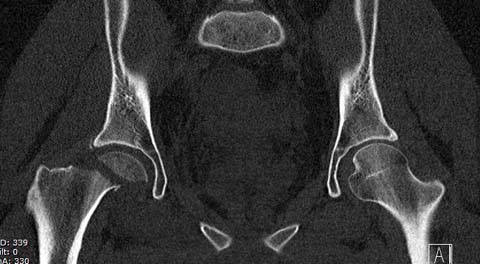

Здесь клинические примеры: Первый случай передний доступ, второй с ICP

monitor Flipp Trochanteris

и с переломом заднего края.